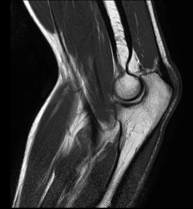

Exploració ideal per estudiar les lesions en músculs isquiotibials i quàdriceps, sovint lesionats en esportistes. També permet una bona valoració de tendons i de nervis perifèrics. La durada aproximada és de 20 minuts. No utilitza radiació ionitzan. - RM de Genoll

Exploració per estudiar lesions a l'articulació, com trencaments dels meniscals i dels lligaments creuats (únicament es poden detectar amb aquesta prova), condropatia o desgast del cartílag i moltes altres alteracions derivades de l'activitat esportiva i dels canvis degeneratius (osteoartrosi). La durada aproximada és de 18 minuts. No utilitza radiació ionitzant. - RM de Cama